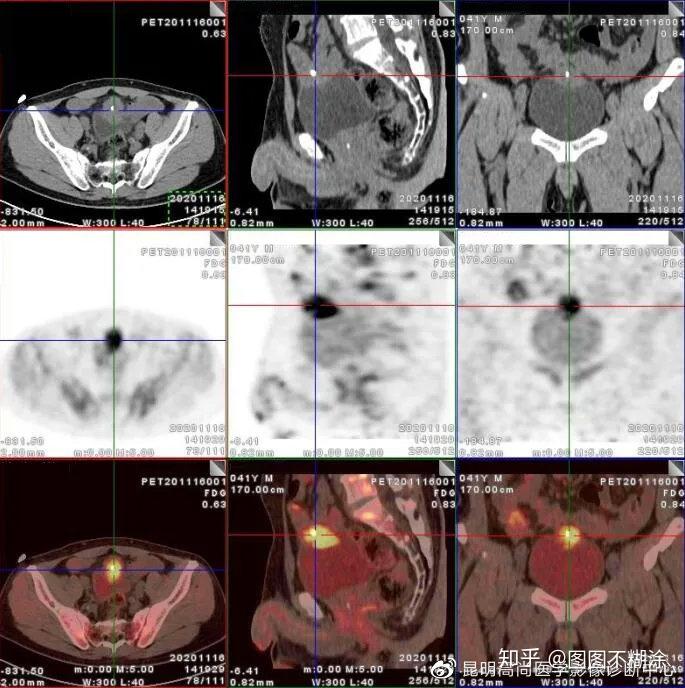

区及膀胱顶前壁软组织肿块,代谢增高,考虑脐尿管恶性肿瘤(脐尿管癌)